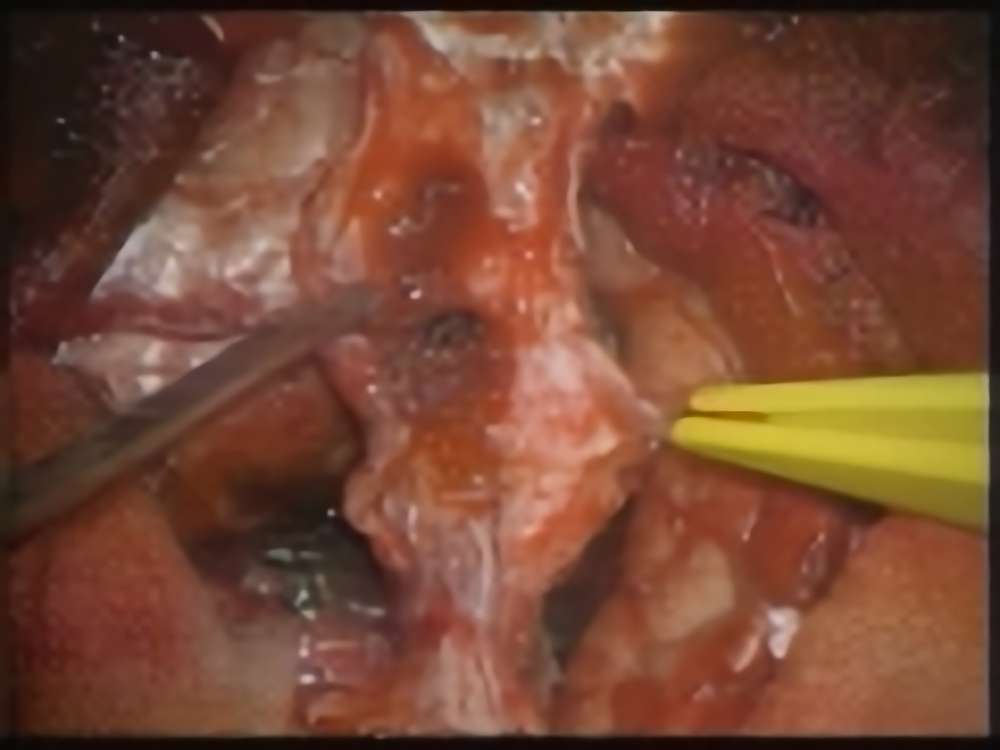

髄膜腫

術中写真

摘出 中

No.’16_114 摘出 後